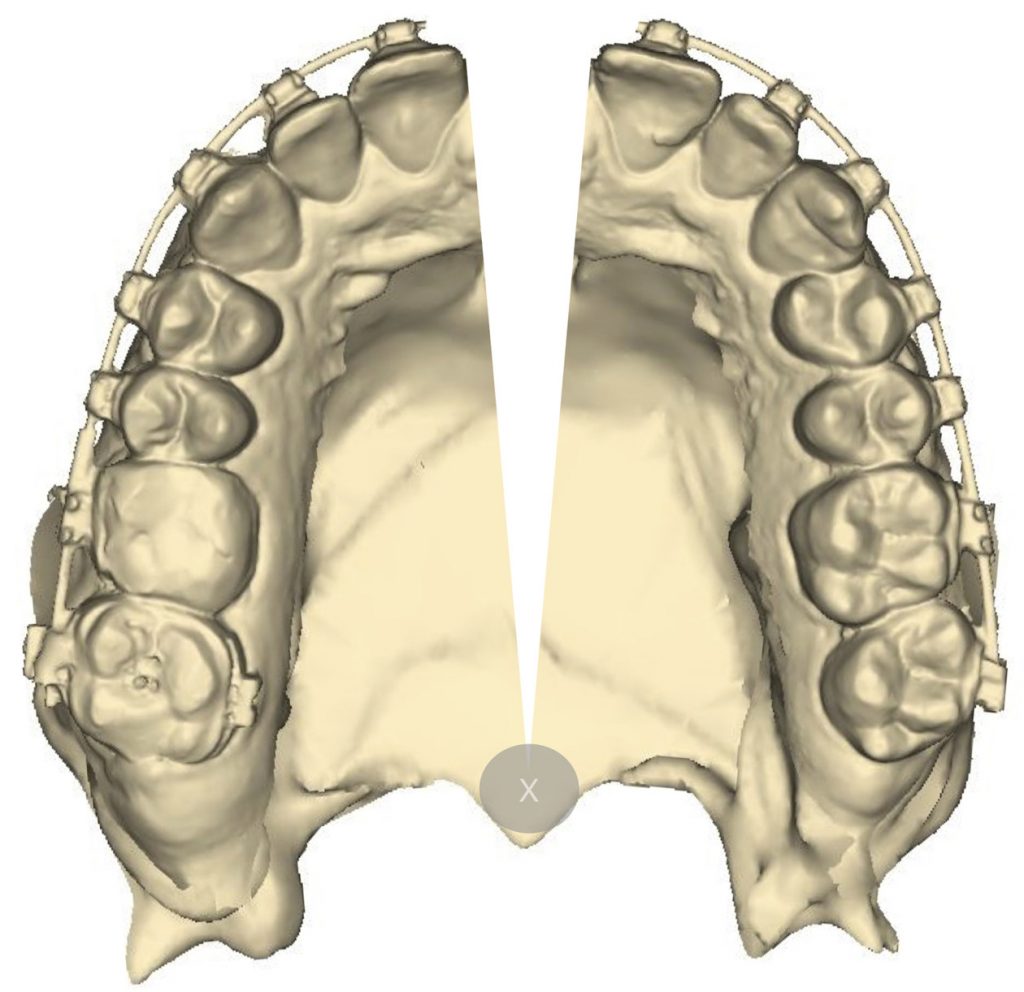

- Obrazowanie za pomocą zdjęć rentgenowskich.

Streszczenie: Chirurgicznie wspomagane poszerzenie szczęki (surgically assisted rapid maxillary expansion – SARME) stosowane jest przy leczeniu szkieletowych zaburzeń wymiarów poprzecznych szczęki u pacjentów dorosłych. Procedura ta oprócz poprawy warunków zgryzowych i estetycznych ma również wpływ na czynność układu stomatognatycznego – napięcie mięśni, funkcję języka i warg oraz oddychanie. Celem pracy było zgromadzenie współczesnych wyników badań na temat wpływu SARME na wymiary górnych dróg oddechowych na poziomie jamy nosowej oraz trzech pięter gardła. Do przeglądu piśmiennictwa zakwalifikowano oryginalne prace badawcze opisujące badania, w których zastosowano aparaty poszerzające szczękę, oraz dokonano oceny górnych dróg oddechowych za pomocą rentgenodiagnostyki, tomografii komputerowej, rynometrii akustycznej lub rynomanometrii. Przedstawione wyniki badań zwracają uwagę na wpływ leczenia ortodontyczno-chirurgicznego na struktury przestrzeni laryngologicznej, poprzez zwiększanie ich wymiarów. Długoterminowa stabilność tych zmian wymaga dalszych badań.

Procedura szybkiego poszerzenia szczęki (rapid maxillary expansion – RME) jest wykorzystywana w leczeniu deficytu szerokości szczęki. Po raz pierwszy zaprezentowana została przez Angella [1] w 1860 roku, ponownie przedstawiona została przez [...]